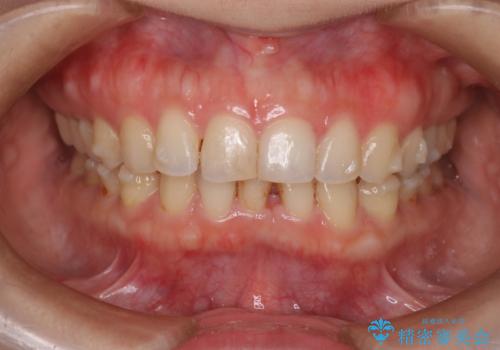

- 下顎前歯の叢生を主訴に来院されました。

臼歯関係の状態から下顎前歯一本の抜歯を行う治療計画を立て、インビザラインを使用して治療を行いました。

今回の抜歯ケースはインビザラインでも綺麗に治ります。